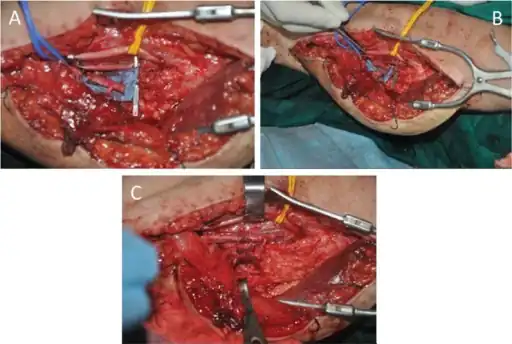

Flow-through anastomosis of the T-shaped pedicle. A) The diameter of the profunda femoris segment is obviously larger than that of the nutrient artery of the gracilis. B) The brachial artery was resected, and the diameters of the segment profunda femoris and brachial artery were well matched. C) Interposed anastomosis to bridge the brachial artery. Two veins were anastomosed in direct end-to-end fashion.

Flow-through anastomosis of the T-shaped pedicle. A) The diameter of the profunda femoris segment is obviously larger than that of the nutrient artery of the gracilis. B) The brachial artery was resected, and the diameters of the segment profunda femoris and brachial artery were well matched. C) Interposed anastomosis to bridge the brachial artery. Two veins were anastomosed in direct end-to-end fashion.